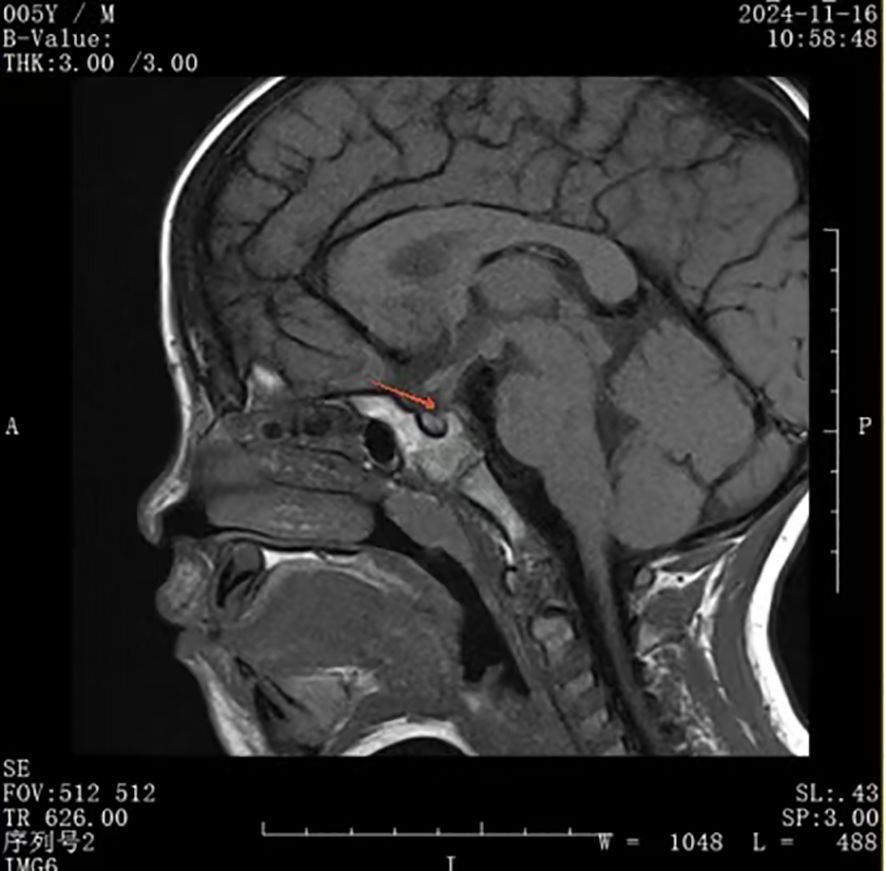

Rationale: SARS-CoV-2 infection can directly and indirectly affect the nervous system, including the hypothalamus and pituitary, and potentially cause IgG4-related hypophysitis. Patient concerns: A 4-year-old Chinese boy presented with arginine vasopressin deficiency (AVP-D, previously called 'central diabetes insipidus') and significant growth retardation. MRI indicated thickening of the pituitary stalk and alterations in the posterior pituitary. Diagnosis: The boy experienced polydipsia, polyuria, and enuresis 4 months after infection by SARS-CoV-2 and 2 months prior to presentation in June 2023. The diagnosis was IgG4-related hypophysitis, AVP-D, and growth hormone deficiency. Treatment with glucocorticoids and desmopressin led to significant resolution of symptoms and normalization of pituitary morphology. However, a second SARS-CoV-2 infection was followed by recurrence of polydipsia, polyuria, and thickening of the pituitary stalk. This recurrence led to a final diagnosis of IgG4-related hypophysitis caused by SARS-CoV-2 infection. Interventions: Glucocorticoids and desmopressin alleviated the AVP-D. Growth hormone and a diet and exercise plan were recommended to manage his short stature. We plan to conduct a functional assessment of the gonadal axis after he is 6 years old. Outcomes: After 18 months, the polydipsia and polyuria were controlled, and an MRI showed significant thinning of the pituitary stalk. This is the first reported case of lgG4-related hypophysitis in a Chinese boy infected with SARS-CoV-2. Lessons: We successfully controlled clinical symptoms, but further follow-up observations are needed to assess recovery. Although the role of SARS-CoV-2 infection in this patient's condition is only suggestive, other reports have described a relationship between SARS-CoV-2 infection and lgG4-related hypophysitis.